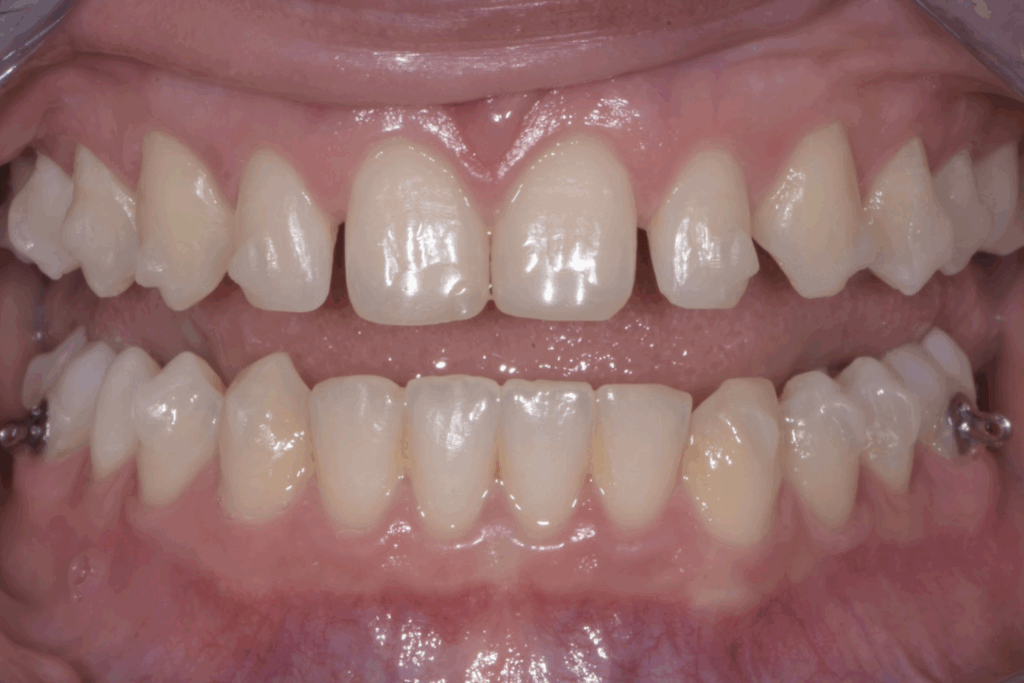

A 17 anni, una paziente si è rivolta al nostro studio con l’obiettivo di migliorare il proprio sorriso e la funzionalità masticatoria. Il caso clinico presentava una combinazione di problematiche comuni e complesse: agenesia dei settimi inferiori, incisivi superiori di piccole dimensioni e un morso profondo. Questa situazione non solo comprometteva l’estetica del sorriso, ma poteva causare problemi funzionali a lungo termine. La soluzione scelta per questa giovane paziente è stata un approccio combinato di ortodonzia moderna con allineatori trasparenti e odontoiatria estetica conservativa.

La prima fase del trattamento è stata un’analisi approfondita. Durante il check-up, abbiamo confermato la diagnosi di agenesia dei secondi molari permanenti inferiori, una condizione congenita che lascia spazi vuoti nell’arcata. Abbiamo inoltre rilevato che gli incisivi superiori erano di dimensioni ridotte rispetto al resto dei denti e che la paziente presentava un morso profondo, con gli incisivi superiori che coprivano eccessivamente quelli inferiori. Questa valutazione completa ci ha permesso di creare un piano di trattamento personalizzato e preciso, tenendo conto di tutte le problematiche presenti.

Risultato finale